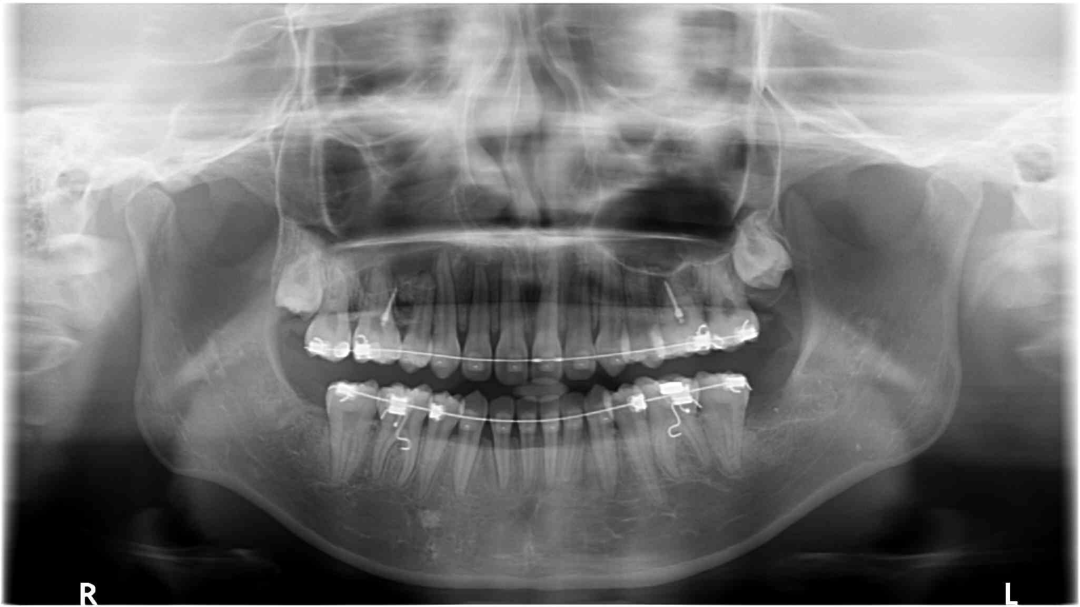

全景片

牙根基本平行,未见牙根吸收